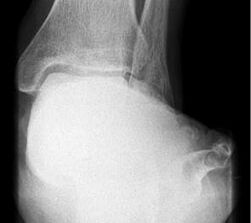

Abbildung Nr. 1: Röntgen Fuß: dp und seitlich stehend.

Abbildung Nr. 2: Saltzmannaufnahme zur Bestimmung des Fersenvalgus.

Es konnte, bei präoperativer Unfähigkeit zum einbeinigen Zehenspitzenstand, beim letzten Follow up in 62% der Fälle ein schmerzloser einbeiniger Zehenspitzenstand erreicht werden. Der Saltzmann-Winkel konnte von präoperativ 11° (7-17°) auf 3° (1-8°) korrigiert werden. Der seitliche Metatarsale I Winkel wurde von 18° präoperativ (13-23°) auf 7° (5-13°) postoperativ korrigiert. Der talonaviculare Überdeckungswinkel konnte von präoperativ 10° (4-18°) auf postoperativ 7° (2-15°) reduziert werden.